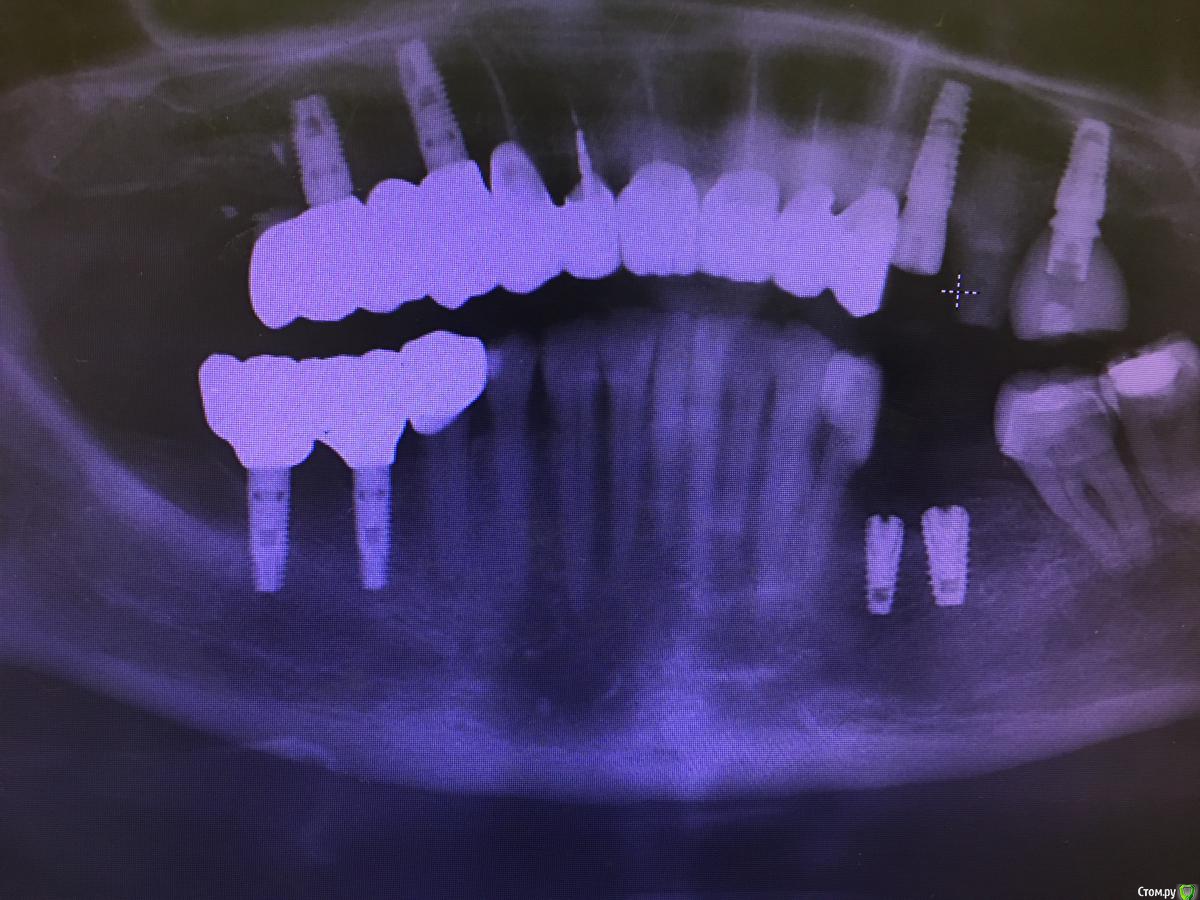

ilnurik Опубликовано 16 сентября, 2020 Поделиться Опубликовано 16 сентября, 2020 (изменено) Коллеги. Сегодня установил два имплантанта, на оптг обнаружил, что импланты близко друг к другу, сразу переставлять не стал. Можно ли переставить на следующий день чуть дистальнее?Фото есть. Оптг только завтра могу скинуть. Изменено 16 сентября, 2020 пользователем ilnurik Ссылка на комментарий

ilnurik Опубликовано 17 сентября, 2020 Автор Поделиться Опубликовано 17 сентября, 2020 Загрузил оптг. Близко? Переставить или оставить?Быть или не быть ? 1 Ссылка на комментарий

red_butler Опубликовано 17 сентября, 2020 Поделиться Опубликовано 17 сентября, 2020 Я бы не переставлял, но импланты нужно сильнее заглубить, и мне видеться что заглушка на первом импланте не докручена 1 Ссылка на комментарий

ilnurik Опубликовано 17 сентября, 2020 Автор Поделиться Опубликовано 17 сентября, 2020 Я бы не переставлял, но импланты нужно сильнее заглубить, и мне видеться что заглушка на первом импланте не докрученаЯ в этом месте делал аугментацию по ширине ламинатом, три месяца назад. Кость мягкая, со свёрла собрал и заложил между ламинатом и имплантом. Сверлил без ирригации. Имплантаты на 1мм ниже вестибулярной стенки стоят. Дальше глубить не стал, близость мандибулярного спугнула. Торк получился хороший, по ощущениям заглушки докрутил, а сейчас вы сказали, посмотрел, действительно, не докручен. На осмотр приходила. Переставлять, трогать не стал. Ссылка на комментарий

Irouil Опубликовано 17 сентября, 2020 Поделиться Опубликовано 17 сентября, 2020 Да, надо было ещё приглубить 1 1 Ссылка на комментарий

TIGER Опубликовано 25 сентября, 2020 Поделиться Опубликовано 25 сентября, 2020 это к вопросу о необходимости навигации....этот случай показателен,уже оставляйте как есть Ссылка на комментарий